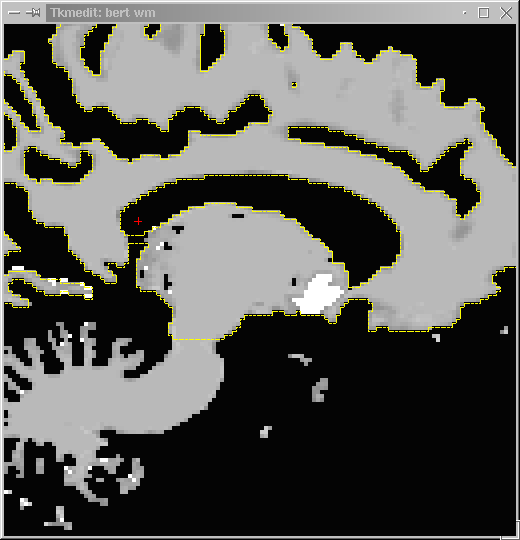

The final step of the Process Volume procedure, Segment White Matter, segments the white matter leaving the wm volume that can be viewed using tkmedit. This last step takes approximately 20 minutes/hemisphere.

The wm volume is now ready to view:

TkMedit reads a maximum of two volumes at a time. The images in the first buffer can be edited and saved, whereas images loaded into the second buffer are view-only and cannot be edited. The second buffer is useful for comparative analyses, (e.g. when the first buffer has segmented white matter (wm volume) and the second buffer has the original T1 images). It is recommended that you load in the T1 volume as your second volume (auxiliary to the wm volume) to refer to when you make your edits.

Now you are ready to edit voxels and display your main (wm) and auxiliary (T1) volumes.

Continue to fill in the lateral ventricle in the wm volume, zooming in to help you see the defect. You may opt to fill in the lateral ventricle of the other hemisphere at the same time, when you become more proficient. The disadvantage of doing so is that TkMedit can only load the orig surface (overlaid in yellow) for one hemisphere at a time, making it sometimes hard to identify the outline of the orig surface (what has been segmented as wm) in the hemisphere that doesn’t have its orig surface overlaid.